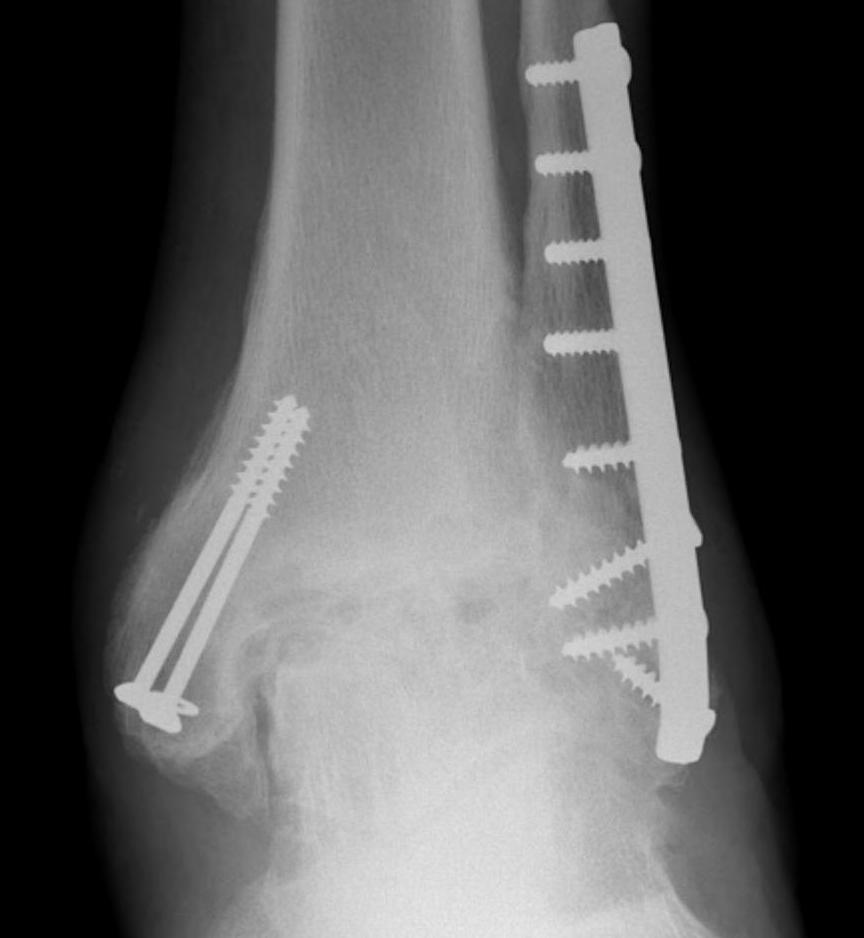

1. Loosening

2. Infection

3. Instability

4. Periprosthetic fracture